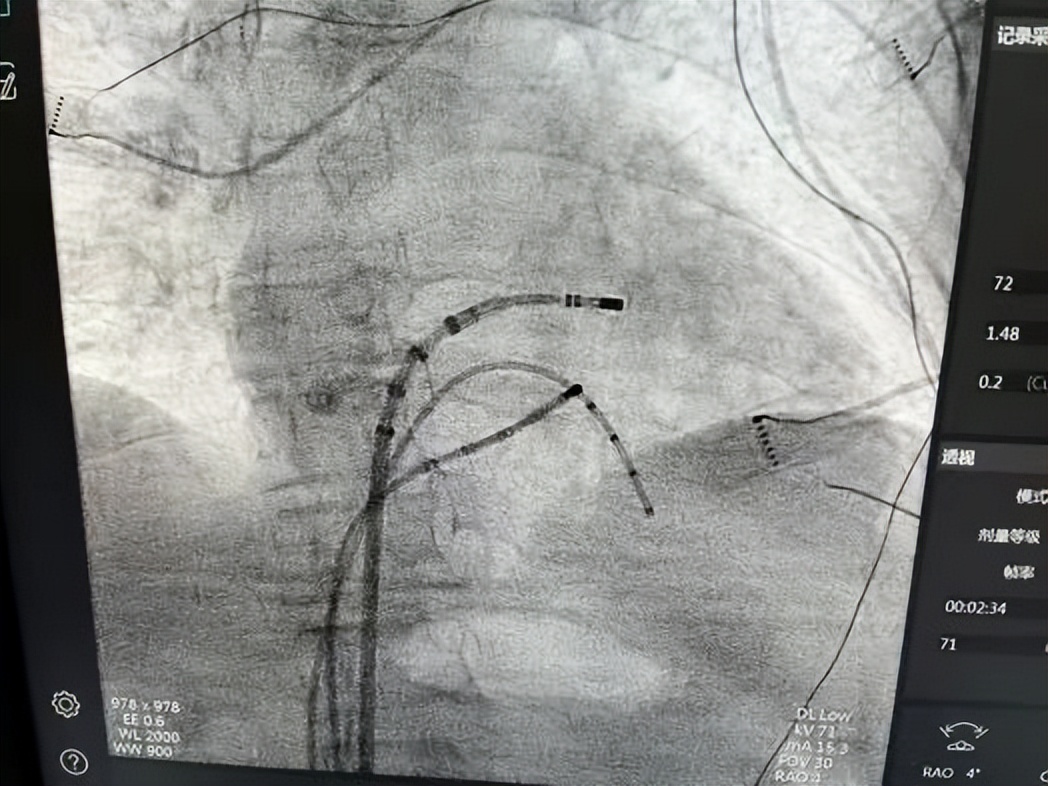

△ 手术导管图

术中,医生在三维标测系统和心腔内超声的双重指引下,像“拆炸弹”一样精准定位病灶,整个过程顺利完成。

微创无痛恢复快:仅需穿刺静脉血管,将导管送入心腔,释放射频电流“消除”异常病灶;